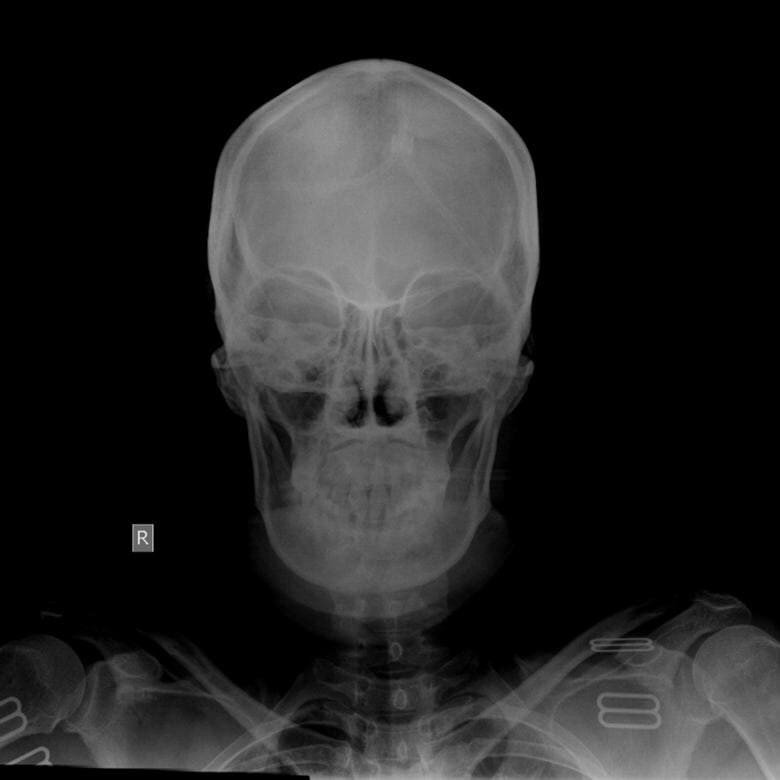

Перелом черепа на КТ

КТ головного мозга является приоритетным методом диагностики при травме черепа. Основными доводами в пользу компьютерной томографии выступают высокая точность отображения черепных пластин, способность показать состояние головного мозга и быстрота проведения сканирования. При помощи компьютерного томографа сканирование проходит за 1-3 минуты. Несмотря на кратковременность обследования данные томографии максимально информативны и точны, чтобы судить о характере повреждения черепных пластин, последствиях перелома и его тяжести. КТ или рентген черепа - что лучше? КТ черепа и рентгенография - это два основных способа визуализации черепных пластин. При черепно-мозговой травме КТ-исследование является приоритетным методом сканирования. Компьютерная томография способна точно считать повреждения черепа, которые на рентгеновских снимках могут остаться не замеченными, поскольку КТ черепа дает трехмерную, а не двухмерную картину обследуемой области как при рентгене. Кроме того, результаты томограф

При черепно-мозговой травме КТ-исследование является приоритетным методом сканирования. Компьютерная томография способна точно считать повреждения черепа, которые на рентгеновских снимках могут остаться не замеченными, поскольку КТ черепа дает трехмерную, а не двухмерную картину обследуемой области как при рентгене. Кроме того, результаты томографического сканирования не только покажут состояние основания черепа, его свода, костей, но и головного мозга. Это позволит провести комплексную оценку повреждений при ЧМТ как костных, так и мягкотканных структур.

Сканирование покажет настоящую картину повреждения костей черепа:

• Выявит перелом основания черепа;

• Отобразит на снимке перелом свода черепа;

• Зафиксирует перелом височной кости и его разновидности.

На КТ снимках можно абсолютно точно рассмотреть состояние черепа, изменение костей при травме. Врач безошибочно определит такие параметры, как:

• Характер и направление перелома;

• Количество, размеры, а также расположение отломков;

• Внешний вид отломанных костных тканей;

• Глубину вдавленных отломков.